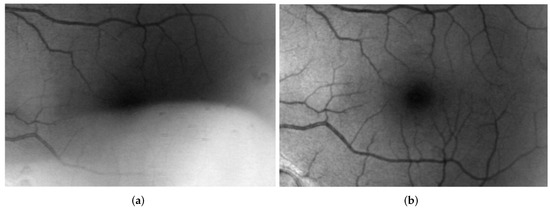

There are many methods for calculating the contrast in images, and the measurement of contrast is a critical parameter in the analysis of biomedical images [29]. The absolute mean intensity difference between the white foreground and the black background of the image is used to calculate the contrast in retinal fundus images and MR brain images. Figure 3 shows the contrast determination of the retinal fundus images and the brain MRI. The left hand image in Figure 3 shows the contrast between the blood vessel and its background on the retinal fundus image. The right hand image in Figure 3 shows the contrast between the white foreground and the black background on the brain MRI.

Figure 3.

Contrast Determination of Retinal Fundus Images and MRI Brain Images. The left hand image shows the retinal fundus image contrast calculation, and the right hand image represents the MR brain image contrast calculation.

In Figure 3, the blue dots represent the blood vessel pixel value from the retinal fundus images, and the red represent the background pixel values. The blue dots in Figure 3 represent the pixel value in the foreground white planes of the brain MRI, and the red dots in Figure 3 represent the black plane of the brain MRI. The mathematical representation of the contrast is shown in Equation (3).

The contrast of the brain MRI is measured between the foreground (colored white, and it is also called foreground white) and the background (colored black, and it is also called background black). The retinal image contrast is measured between the retinal blood vessels (in the foreground) against the background of the retinal vessels. The contrast in the two images (retinal and brain) is represented by . The intensities of the retinal blood vessels or the white foreground of the MR brain image and the intensities of the background against the blood vessels or intensities of the black background of MR brain images are represented as and , respectively. The variable n indicates the number of pixels, where n = 200. The pixel locations for measuring the contrast were chosen at random.